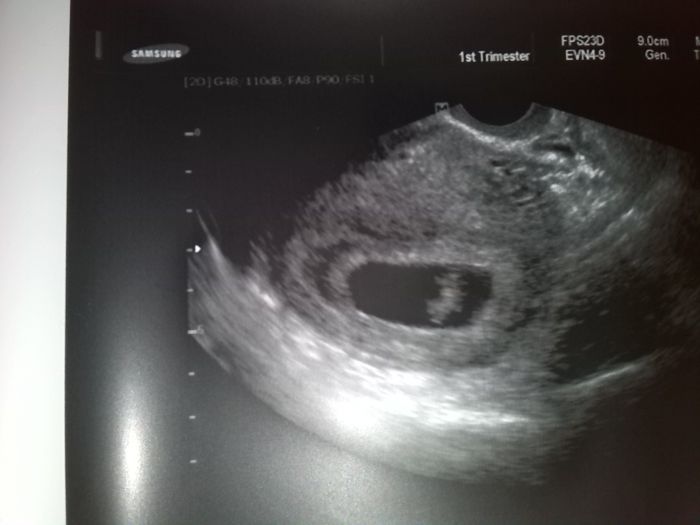

[417985] ta bila tecka na hrudnicku je srdicko :-)

nádherná bublinka! ty jo to ten tejden bude ještě delší